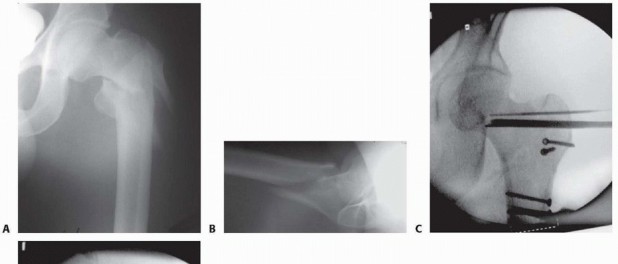

### TECH FIG 3 • Implant insertion. A. Lag screw and side plate on inserter. B. Placement of side plate. C. Implant in place. D. Traction released. E. Fracture after compression. A triple reamer is used to prepare the channel in the lateral cortex, neck, and head for the lag screw and side plate barrel. The reamer is set to 5 mm less than the measured lag screw length to ensure that the subchondral bone in the femoral head is not violated during reaming. The triple reamer is then advanced and withdrawn under fluoroscopic guidance. It is important to use fluoroscopy during reaming to ensure that the guide pin is not bonded to the reamer and inadvertently advanced into the pelvis. The channel is reamed to its proper length and removed under fluoroscopic guidance, ensuring that the guide pin is not withdrawn with the reamer. An obturator may be used to help prevent the pin from backing out. Occasionally, the intact lateral wall of the proximal femur may be fractured by the triple reamer. If this occurs, the fracture is essentially converted into a transverse or reverse oblique pattern (AO/OTA type 31-A3), and excessive fracture collapse will occur if fixed only with a sliding hip screw. In these cases, the proximal lateral wall may be buttressed with the addition of a trochanteric stabilizing plate in conjunction with a sliding hip screw. Alternatively, the decision may be made to convert to an intramedullary device for fracture fixation. ### Implant Insertion A two- to four-hole side plate is usually chosen for fixation ( TECH FIG 3). Multiple clinical and cadaveric studies have shown no difference in the strength of implant fixation with side plates with more than four holes. 3, 10 The implant is set up according to the manufacturer's specifications. The cannulated lag screw is then inserted over the guide pin with a centering sleeve to ensure proper positioning. Careful sizing of the lag screw length is required, as noted earlier, to ensure that fracture compression does not lead to excessive screw length and lateral hardware prominence. 409 Fluoroscopy and manual fracture palpation are used to ensure that the fracture is not displaced (rotated) while the lag screw is inserted. If the fracture is displaced by the insertion of the lag screw, it is removed, a derotation screw is added, the channel is tapped, and the lag screw is reinserted. Peritrochanteric fractures of the right hip tend to displace to an apex posterior angulation as the lag screw is turned clockwise during insertion, whereas left hip fractures tend to displace to an apex anterior angulation owing to the anatomic configuration and subsequent tensioning of the hip capsule with screw insertion. With the lag screw inserted to the desired depth within the femoral head on the AP and lateral fluoroscopic projection, its relation to the lateral cortex is checked to ensure proper length. Ideal position of the distal tip of the screw is approximately 5 to 8 mm deep to the lateral cortex. The side plate is then slid over the lag screw and inserter so it is seated on the lateral cortex, and the guide pin (and derotational pin if used) is removed. Traction is released at this point to allow slight impaction of the fracture in the axial plane. Cortical screws are inserted to secure the plate to the femoral shaft. If appropriate for the fracture pattern, the lag screw compressing screw is then inserted into the barrel of the lag screw and tightened to compress the fracture in the plane of the lag screw, under fluoroscopic guidance. The compression screw may be removed in certain cases. If the fracture is oriented such that weight bearing will cause compression at the fracture site, it is reasonable to remove the compression screw. It is mandatory to use and retain the compressing screw in paralytics, where there is no resting joint reaction force, and implant disengagement can occur with postoperative transfers. With the compression of the fracture complete, the alignment and implant position are checked once again with fluoroscopy. 1. ## Blade Plate ### Approach A lateral approach is used, as described earlier. Although the incision is more proximal, and angles toward the anterior superior iliac spine, the trochanteric block must be exposed and interval between tensor and gluteus medius must be exploited in order to visualize anterior neck. ### Preparation and Implant Insertion With the lateral femur and trochanteric block exposed, if a direct reduction is desired, a soft tissue-sparing reduction of the trochanteric block to the proximal femur is secured with pointed bone clamps and K-wires or small lag screws ( TECH FIG 4). Alternatively, an indirect reduction can be employed, relying on the proper position of the blade within the proximal segment to reduce the fracture when the plate is brought onto the shaft. Guide pins are then introduced into this reconstructed segment to facilitate proper seating of the chisel for the blade plate. The first pin is placed anterior to the femoral neck and secured into the anterior femoral head to demonstrate the femoral anteversion. The second pin is placed with the use of an angled guide and/or fluoroscopy near the tip of the greater trochanter and directed into the femoral head at a 90-degree angle to the femoral shaft. The chisel is inserted parallel to the two guide pins, just distal to the second pin. Care must be taken to maintain the correct alignment of the chisel with the shaft of the femur because this determines the flexion-extension of the fracture, which is fixed once the blade plate is inserted. The chisel is directed so as to pass through the center of the neck and seat in the inferior portion of the femoral head. Because of the anterior translation of the femoral head on the shaft, the insertion site is in the anterior half of the trochanter. The position of the chisel should be constantly checked with fluoroscopy before and during its insertion. The chisel is carefully removed and the appropriate-length blade plate is inserted and gently seated into the proximal fragment. The insertion should be frequently checked with biplanar fluoroscopy to ensure that the blade follows the path made by the chisel. Once the blade is seated, the most proximal screw is placed through the implant into the medial cortex of the proximal femoral neck, rigidly securing the implant to the proximal fragment. Fracture reduction is now achieved by bringing the plate to the shaft and controlling length and rotation. If needed, a femoral distractor may be used as a reduction tool. The distractor should be fixed to the lateral aspect of the femur, with the proximal pin in the head and neck fragment and the distal pin placed distal to the end of the plate. Distraction is applied across the fracture to improve fracture alignment and length through soft tissue tensioning. A bone clamp is loosely applied to the distal femoral shaft fragment and plate to counteract the tendency for the fracture to be reduced into varus with the femoral distractor. Pointed reduction clamps are used to reduce comminuted fragments to the plate without stripping them of soft tissue attachments. Fracture reduction is checked with fluoroscopy. If fracture alignment is acceptable, the distraction is taken off to allow fragment settling and fracture compression. The plate is then fixed to the shaft fragments with screws in the standard manner, and lag screws are inserted where the pointed reduction clamps were previously placed. The final fracture alignment and length, as well as the femoral head, are examined with fluoroscopy to ensure proper fracture reduction and to make sure that there has been no head penetration by the implant. 410

### TECH FIG 4 • Blade plate insertion. A,B. Preoperative AP and lateral radiographs of a type 31-A3 fracture in a 28-year-old man. C. Chisel inserted after femoral head and neck and trochanteric block were secured with lag screws. D. Insertion of blade plate. E. Postoperative AP radiograph. -